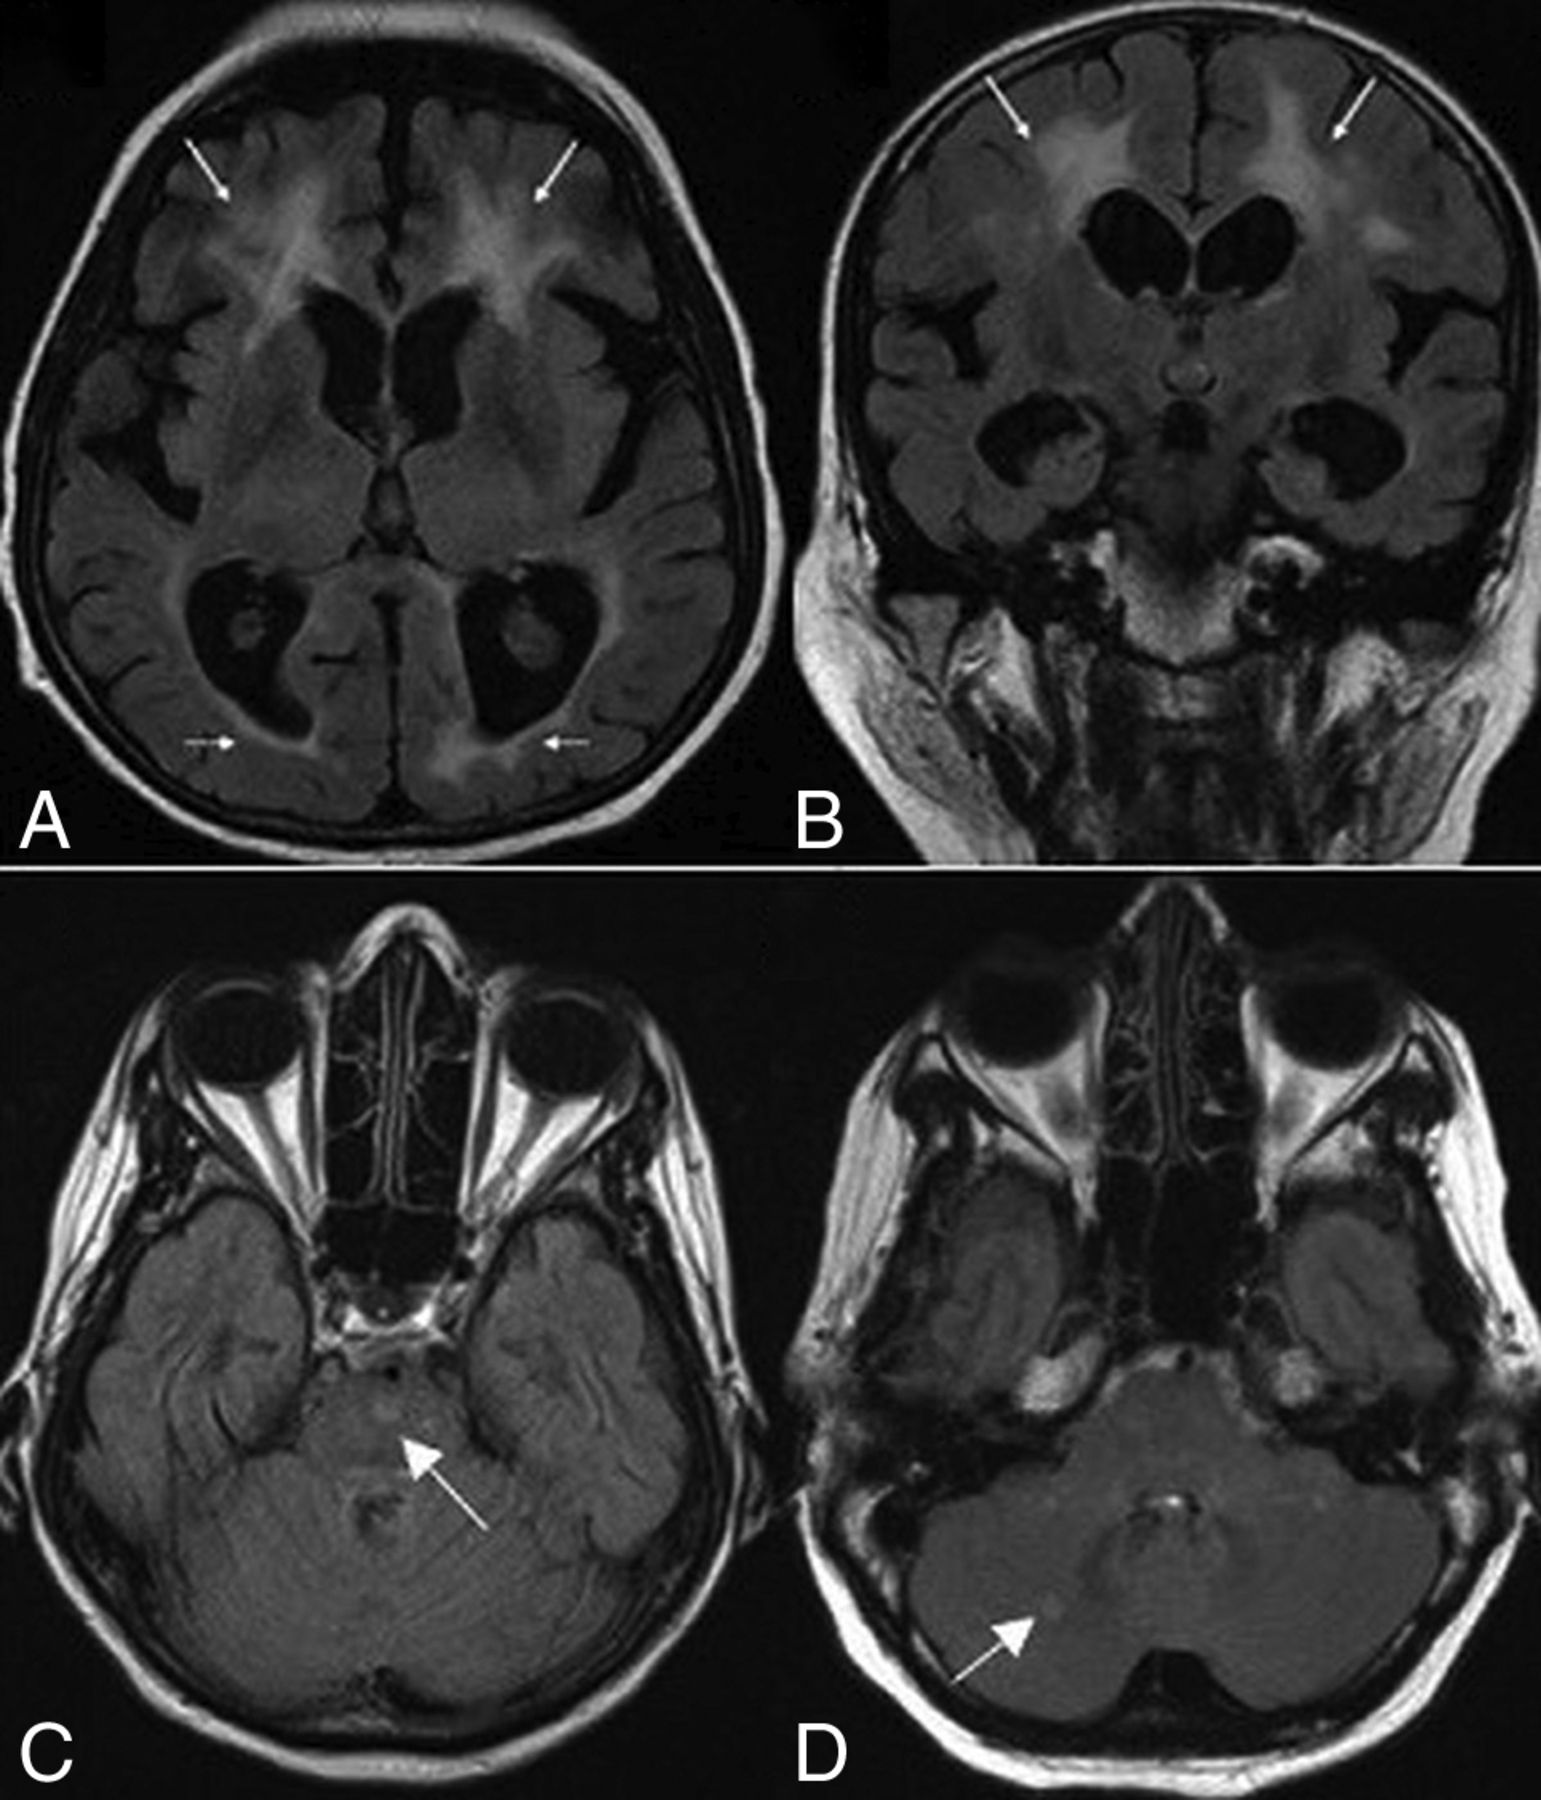

A partially empty sella and a small pituitary gland were seen in 20 patients (76.9%); they were the most common MR imaging abnormalities in our cohort (Fig 1). Patients with WSS had a significantly smaller mean pituitary gland volume of 173 ± 91 mm3 compared with healthy control subjects with a mean of 480 ± 85 mm3 (P < .005). Six patients (23%) had normal pituitary gland volume. The pituitary stalk varied in size, but most of the affected individuals had a relatively small stalk. No abnormal suprasellar and parasellar structures were noted.

Sagittal T1-weighted MR imaging for patient 22 shows a partially empty sella and a small pituitary gland (arrow).

Evidence of iron deposition in the globus pallidus was observed in 19 patients (73%) (Fig 2A–C). Involvement of the substantia nigra and red nucleus was noted in 6 patients (23%) (Fig 2D). MR spectroscopy in 4 patients demonstrated normal major metabolite peaks. Despite the clinical finding of generalized or focal dystonia, 3 patients showed no evidence of iron deposition on MR imaging.

Axial T2-weighted (A), FLAIR (B), and T2* (C) MR images in case 11 show putaminal blooming artifacts (arrows) reflecting iron accumulation. An axial T2* MR image (D) in case 3 shows iron deposition in the substantia nigra (arrowheads).

Axial (A) and coronal (B) FLAIR MR images for case 24 show white matter changes with frontal predominance (arrows). Axial FLAIR images show signal intensities (arrows) involving the pons (C) in patient 19 and the cerebellum (D) in patient 26.